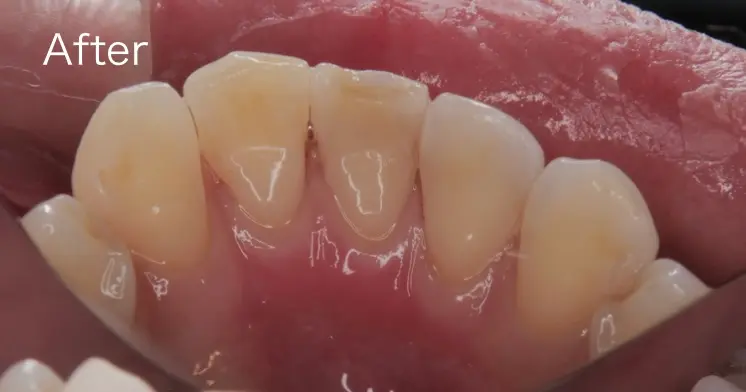

歯石を除去する前とした後の写真です。